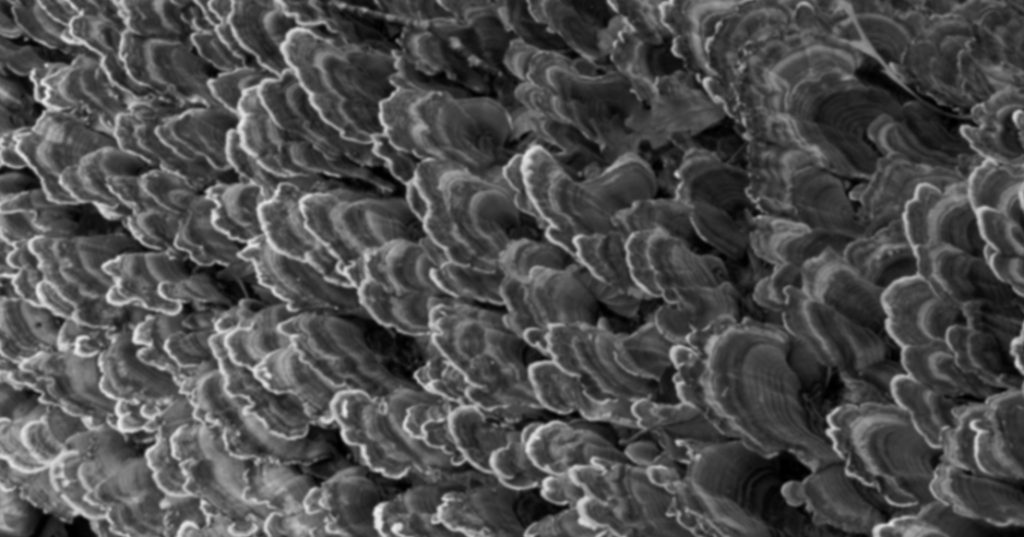

The vertical margin in full veneer crown preparation can offer an esthetic, minimally invasive, and biocompatible solution for periodontally or structurally compromised teeth. For example, this patient, who was restored as a fixed-removable combination case: